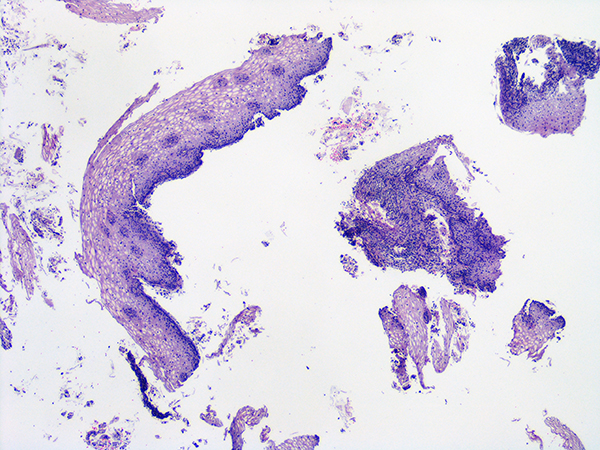

Case 1

Soft Bx CIN 2 10x - Low Power